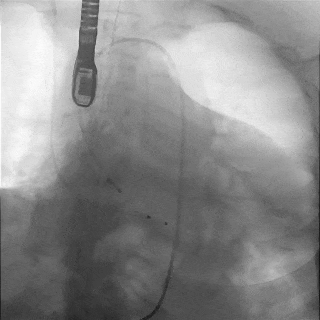

主动脉根部造影

TF29瓣膜,0位定位释放

瓣膜稳定释放至全展开

造影观察:瓣膜位置可,形态佳

左冠切线观察,瓣膜位置可

冠脉灌注良好

缓慢脱钩,瓣膜无位移

脱钩后造影

瓣膜位置可,无瓣周漏

外周造影检查,血管无损伤